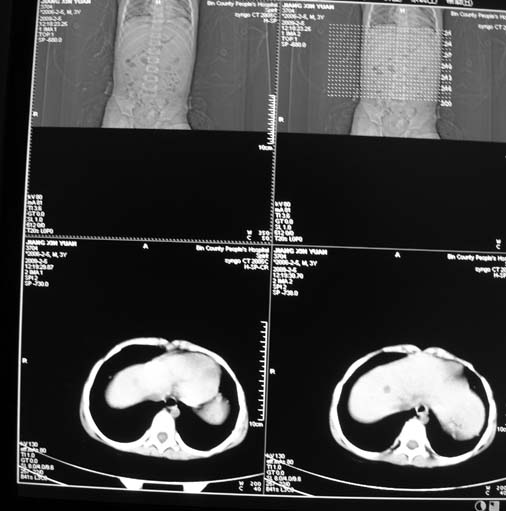

男,3岁,肾母细胞瘤术后,肝脏的低密度是什么?

胰尾下方见两枚囊形灶,肠管?病灶?左侧肾上腺区见团块状影,转移病灶?术后表现?建议与前片对比,肝脏病灶好像有牛眼表现,不除外转移,如果不增强,建议加做个b超,至少可分清其囊性或者实性,又便宜,免费自已给他弄一下也行,对诊断有帮助

左肾母细胞瘤术后:肝脏多发低密度灶,考虑转移可能性大。

左肾母细胞瘤术后:肝脏多发低密度灶,考虑转移可能.请结合临床及增强以及术前检查等